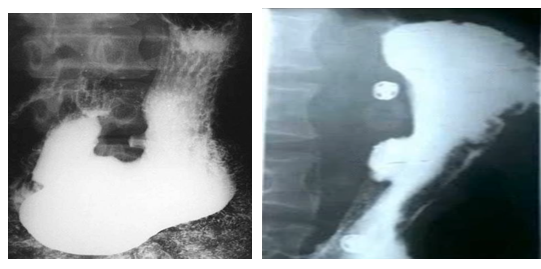

男性,55岁,上腹隐痛约十年,请做出正确诊断

A.胃癌

B.胃溃疡

C.十二指肠溃疡

D.食管癌

E.胃憩室

【答案】B